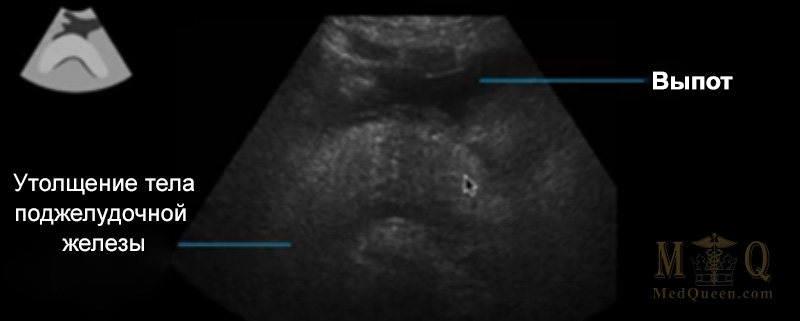

Интерстициальный отечный панкреатит (interstitial edematous pancreatitis-IEP) с гипоэхогенной жидкостью